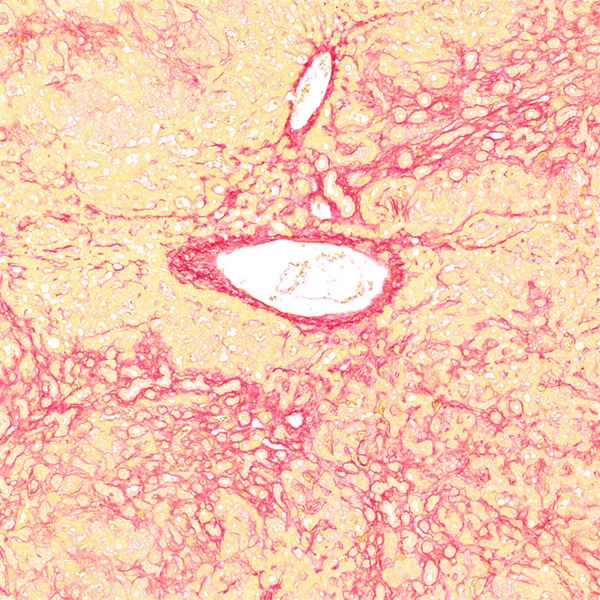

天狼猩红染色

天狼猩红和KWS都是强酸性染料,易与胶原分子中的碱性基团结合,吸附牢固。偏振光镜检查,胶原纤维有正的单轴双折射光的属性,与KWS-天狼猩红结合,可增强双折射,提高分辨率,从而区分两型胶原纤维。未脱钙骨组织切片经天狼猩红染色后,普通光学显微镜下,胶原纤维呈红色或鲜红色,其他呈黄色;在偏振光显微镜下,Ⅰ型胶原纤维呈强橙黄色或亮红色,Ⅲ型胶原纤维呈绿色。

实验结果展示:

<天狼星红-肝>